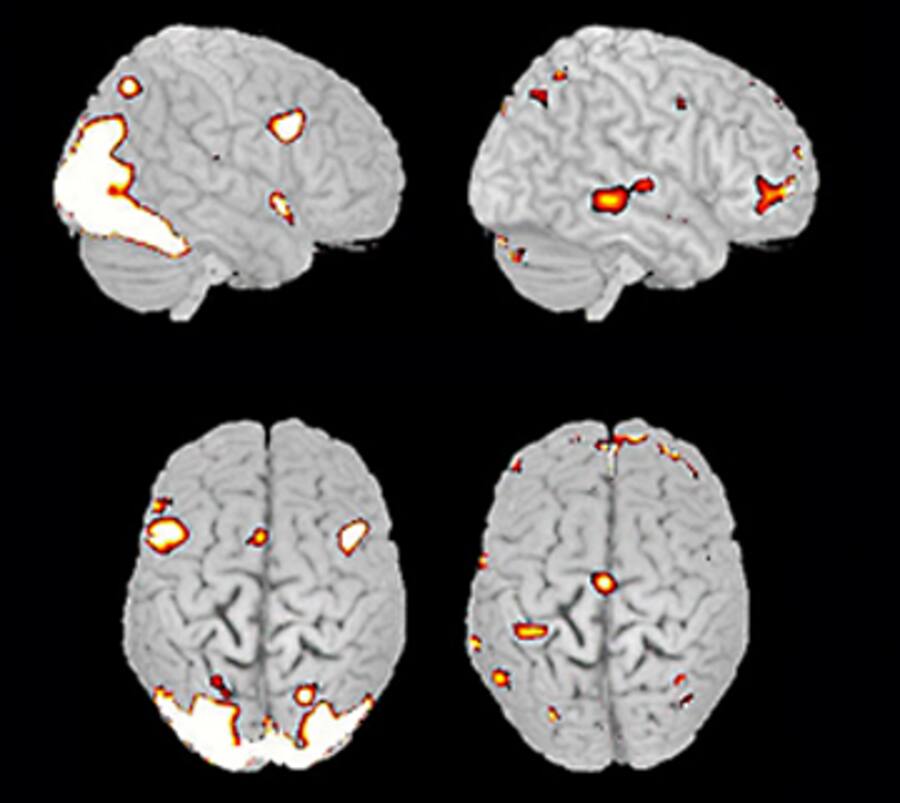

Als Vertreter der Neuropsychologie glaubt Seifritz, dass man nur die richtigen Analysewerkzeuge entwickeln muss, und schon könne man alle psychischen Phänomene erklären. Das Herzstück der noch jungen Wissenschaft ist die Bildgebung. Dabei wird das Gehirn mit Hilfe von Computertechnik abgebildet. So will man nicht nur verstehen, wie das Gehirn aufgebaut ist und wie es funktioniert, sondern auch, welche Prozesse bei psychischen Erkrankungen genau ablaufen. Das Problem dabei: Die Bilder, die die funktionelle Magnetresonanztomographie liefert, zeigen bloss, wie hoch die Konzentration des im Blut gelösten Sauerstoffs ist. Daraus lässt sich auf die Aktivität der jeweiligen Nervenzellengruppen bestimmter Hirnregionen schliessen. Hohe Aktivität ist auf den Bildern rot eingefärbt, niedrige blau.

Tomographie: Farblich markiert sind die aktiven Nervenzellengruppen bei einem Gesunden und einem Patienten mit Depressionen (rechts) beim Betrachten emotionaler Bilder.